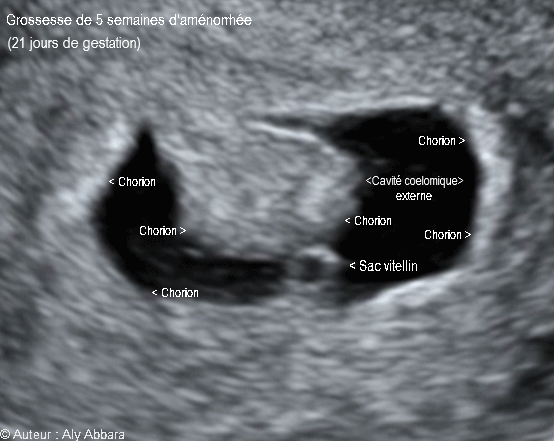

• • Images échographiques montrant un sac gestationnel évoluant dans la cavité utérine correspondant à 20 à 21 jours de gestation (soit la fin de la 5e semaine d'aménorrhée).

• Ces images montrent un sac gestationnel composé essentiellement :

° d'une cavité cœlomique externe limitée par le chorion qui s'insère sur l'endomètre ; cette cavité cœlomique externe contient :

* Seulement le sac vitellin sans image embryonnaire.